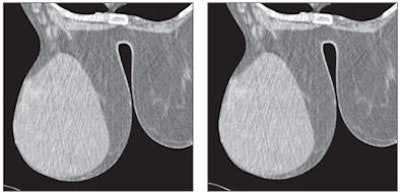

![]()  |

| Forty-six-year-old woman with nonspecific inflammatory tissue in right breast. Dynamic MDCT scans at baseline (left) and one minute after contrast administration (right) show thickened homogeneous tissue beneath the nipple, which exhibited strong enhancement. |